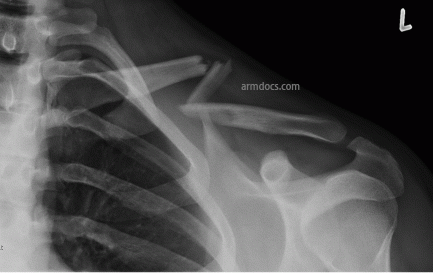

a. Fracture of the clavicle